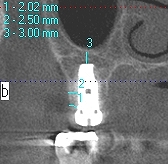

上顎洞への解剖距離が大切です

上顎洞を破ると別の問題が出ます

上顎洞を持ち上げたりします